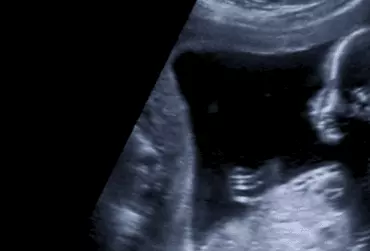

Detekcja aberracji chromosomowych w I trymestrze ciąży za pomocą metod ultrasonograficznych i testów biochemicznych

Opracowanie to przedstawia aktualną wiedzę na temat badań prenatalnych w I trymestrze ciąży. Umożliwiają one rozpoznawanie, diagnostykę i leczenie wad wrodzonych, również zespołów genetycznie uwarunkowanych.

Badania mają na celu zapewnienie optymalnych warunków do rozwiązania ciąży a także opiekę nad kobietą będącą w ciąży i noworodkiem. Badania prenatalne wykonywane w I trymestrze ciąży pozwalają na zidentyfikowanie wad wrodzonych płodu oraz określenie ryzyka najczęściej występujących aberracji chromosomowych.